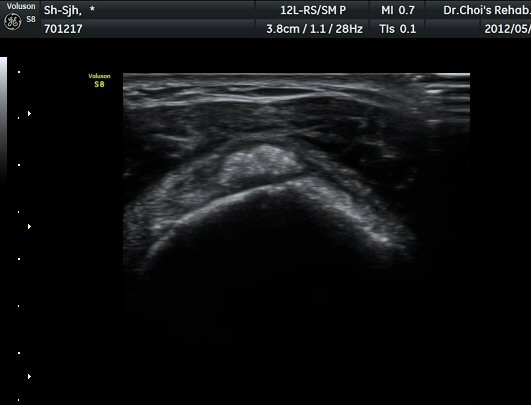

µÈ´Ù(»çÁø 3). ±Ø»ó°Ç Á¾´Ü¸é°Ë»ç»ó ±Ø»ó°Ç ºÎÂøºÎ¿¡ °í¿¡ÄÚ µ¢¾î¸®°¡ °üÂûµÇ°í(»çÁø 4, 5)

ÆÄ¿öµµÇ÷¯ °Ë»ç¿¡¼­ Ç÷·ùÁõ°¡¸¦ º¸ÀδÙ(»çÁø 6).  Ⱦ´Ü¸é°Ë»ç¿¡¼­µµ °í¿¡ÄÚ µ¢¾î¸®¿Í

Ç÷·ùÁõ°¡°¡ È®ÀεȴÙ(»çÁø 7, 8).